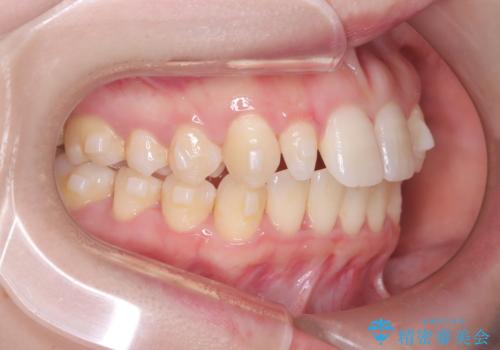

- 歯のデコボコと右上2番の歯の形が気になることを主訴に来院された患者様です。

軽度の叢生(凸凹)であったため、インビザラインのライトパッケージを用いて歯並びを改善しました。その後、右上2番はオールセラミッククラウンにより形態を回復し、審美性を向上させました。